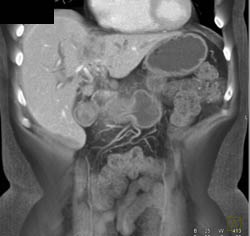

Liver Abscess